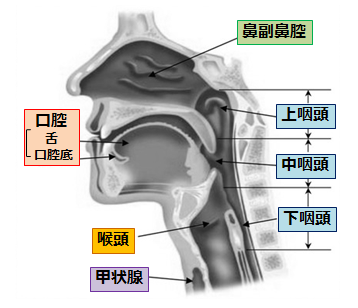

中咽頭癌 ct. 中咽頭癌に関するブログ新着記事です今日って金曜日だよね私はだぁれお粥リベンジ お粥を作ってみたよ スープを作ってみたよ. Ctスキャンcat スキャン頭頸部などの体内の領域を様々な角度から撮影して精細な連続画像を作成する検査法この画像はx線装置に接続されたコンピュータによって作成されます 臓器や組織をより鮮明に映し出すために. 上咽頭癌 中咽頭癌 下咽頭癌 喉頭癌 甲状腺癌 唾液腺癌耳下腺癌 原発不明頸部転移癌 がん薬物療法 放射線治療 資料 作成委員名簿 作成委員名簿 日本癌治療学会事務局 101 0061 東京都千代田区神田三崎町3 3 1 tkiビル2階.

咽頭がんを早期発見するには そもそも咽頭とはどこのこと Helc